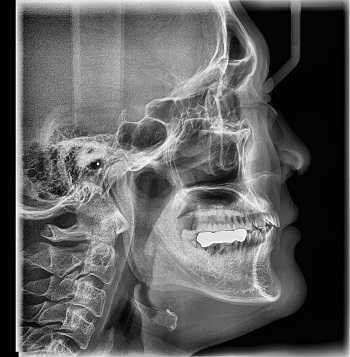

Диагноз «комплексный регионарный болевой синдром» ставится преимущественно на основании клинических проявлений заболевания. Важным диагностическим методом является электронейромиография. Она позволяет определить наличие или отсутствие повреждения периферического нерва. При помощи рентгенографии врачи могут выявить признаки «пятнистого» остеопороза. Врачи Юсуповской больницы применяют современные методы диагностики: компьютерная и магнитно-резонансная томография, трёхфазное радиоизотопное сканирование, термографию.

Рентгенография

Принцип работы рентгеновского аппарата заключается в том, что рентгеновские лучи, проходя через разноплотную среду исследуемой области, по-разному ослабляются: более плотная костная ткань в значительной степени поглощает рентгеновское излучение, менее плотная подкожно-жировая клетчатка ослабляет его в небольшой степени, а воздух, содержащийся в околоносовых пазухах или легких, не задерживает совсем. Эти неравномерно ослабленные пучки рентгеновских лучей, попадая на светочувствительный слой пленки, формируют рентгенограмму — изображение, которое отображает все структуры исследуемой области, наслаивая их друг на друга. При этом получаемый снимок позволяет определить форму, размеры и строение исследуемой области, выявить или заподозрить структурные нарушения, а исследование в двух или нескольких проекциях позволяет определить локализацию выявленных изменений. Чаще всего рентгенография используется для исследования костей, легких, почек, кишечника.